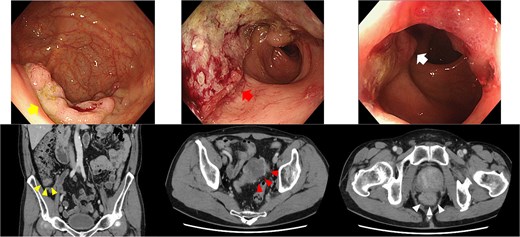

Contrast-enhanced computed tomography (CT) demonstrated bowel wall thickening in all three sites, with regional lymphadenopathy observed in the sigmoid and rectal mesenteries. No distant metastasis was identified (Fig. 1). Given the proximity of the rectal tumor to the anal verge (within 1 cm), sphincter preservation was deemed infeasible, and abdominoperineal resection was planned. Although endoscopic resection was initially considered for the cecal lesion, surgical resection was chosen following multidisciplinary consultation.

Endoscopy and enhanced CT endoscopy showed tumors in the cecum (LST-G, upper left), sigmoid (type 2, upper middle), and rectum (type 2, upper right). Enhanced CT provided important insights into the wall thickness in the cecum (lower left), sigmoid colon (lower middle), and rectum (lower right).